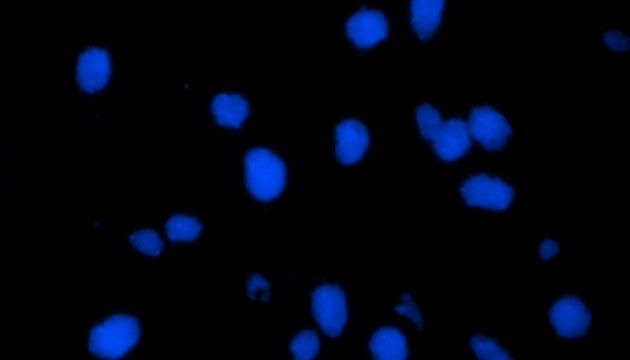

熒光原位雜交(Fluorescence In Situ Hybridization,F(xiàn)ISH)是臨床病理檢測(cè)中廣泛運(yùn)用的一種分子細(xì)胞遺傳學(xué)診斷技術(shù),其原理是用熒光染料直接或間接標(biāo)記的DNA核酸探針與待測(cè)樣本中的DNA核酸序列按照堿基互補(bǔ)配對(duì)的原則進(jìn)行雜交,然后通過(guò)熒光顯微鏡觀(guān)察熒光信號(hào)位置、數(shù)量等來(lái)判斷待測(cè)序列的缺失、擴(kuò)增及易位等情況。其高分辨率、直接反映異常細(xì)胞比例、快速簡(jiǎn)便的特點(diǎn),使其成為臨床檢測(cè)、預(yù)后評(píng)估及用藥指導(dǎo)的重要工具。

FISH技術(shù)面臨熒光弱、背景噪聲、多通道疊加等難點(diǎn)。為了保障熒光信號(hào)強(qiáng)度,一般需要用到研究級(jí)熒光顯微鏡,半復(fù)消色差或以上的物鏡,以及高功率的LED熒光光源或汞燈光源;為了去除背景噪聲,一般需要搭配高截止深度的濾光片和高靈敏度相機(jī);多通道疊加時(shí)要提取紅綠信號(hào)點(diǎn),然后放到藍(lán)色DAPI信號(hào)上,處理需要相當(dāng)?shù)募记伞?